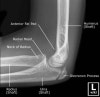

- Elbow Lateral view

2. Elbow AP view

- Elbow Oblique view